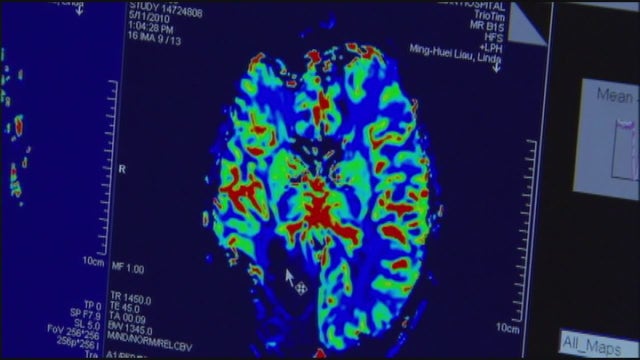

Northwestern Medicine achieves breakthrough in glioblastoma treatment

In what is being hailed as a major breakthrough, scientists from Northwestern Medicine have successfully used ultrasound technology to target and treat glioblastoma, a deadly brain cancer.